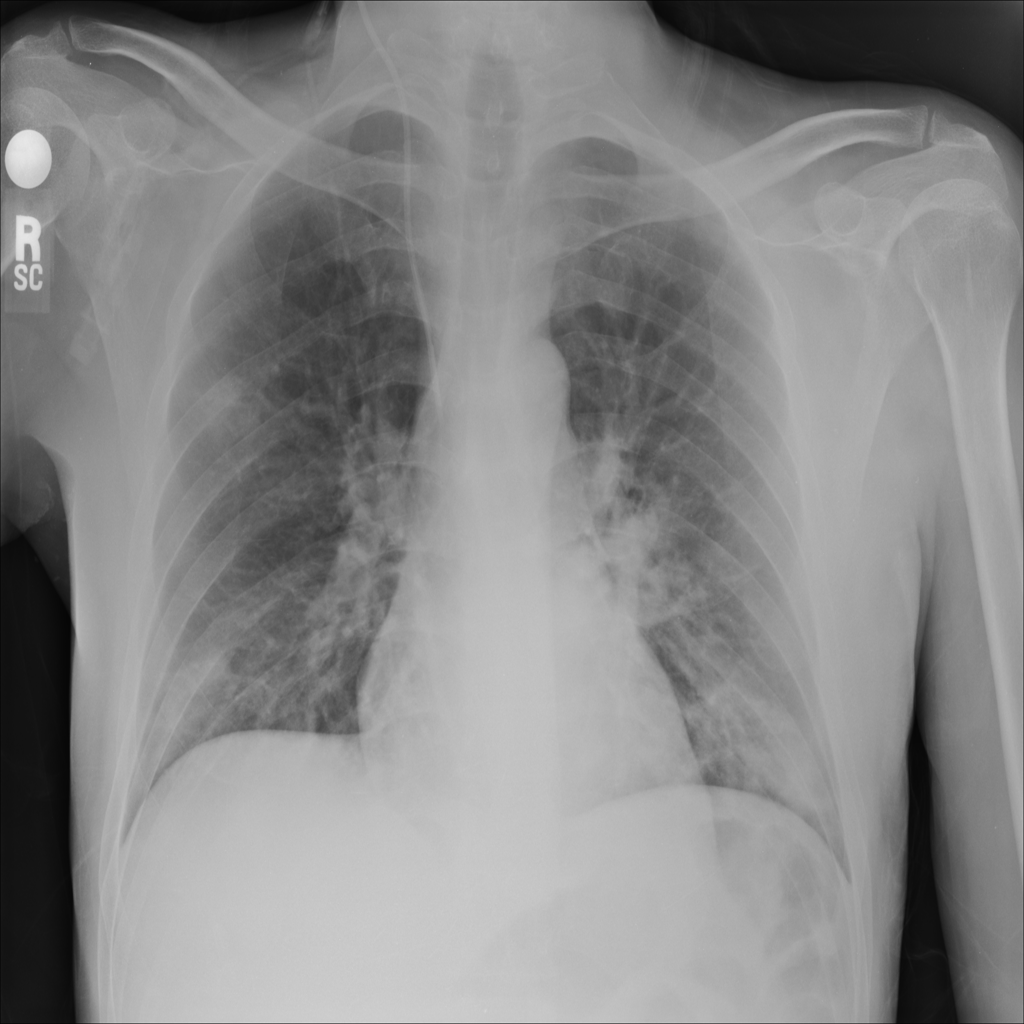

Consolidation

Consolidation refers to air-space filling that makes part of the lung appear denser on imaging.

Showing up to 90 reference images for Consolidation.

PAT-531A · IMG-006Consolidation

PAT-531A · IMG-006

PA